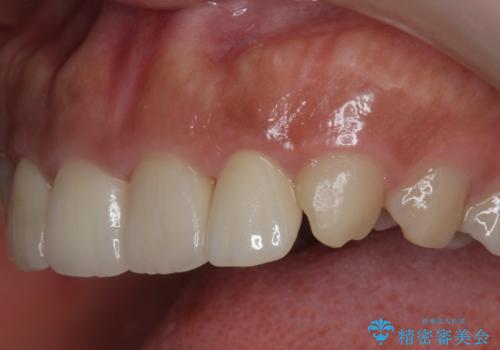

欠けた前歯を綺麗にしたい

- 「欠けてしまった前歯のコンポジットレジン修復をくり返していたが、すぐ外れてしまい困っている。」

、と前歯の欠けの改善を求めて来院されました。

噛み合わせが深く、前歯の突き上げが大きいため欠けの繰り返しを防ぐべくセラミッククラウンによる補綴を行うこととしました。

審美性の改善を達成することができました。